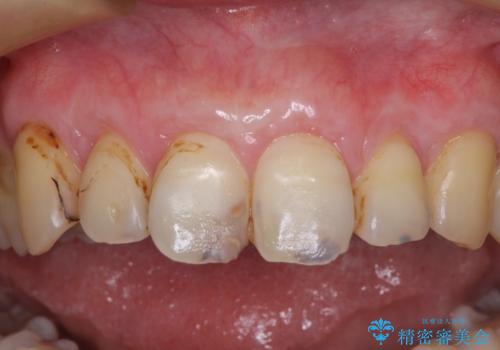

上顎前歯は歯肉退縮により歯根が露出していたため、事前に歯肉移植術により根面被覆を行い、その後にオールセラミッククラウンを装着することとしました。

歯肉移植術による根面被覆を行うかどうかは非常に悩まれていましたが、歯肉が覆われたことで長く見えていた歯の長さが整い、きれいな前歯の仕上がりとなりました。